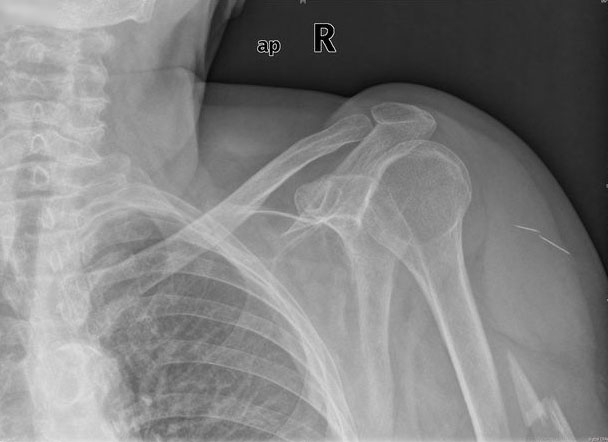

APR Luxación de hombro